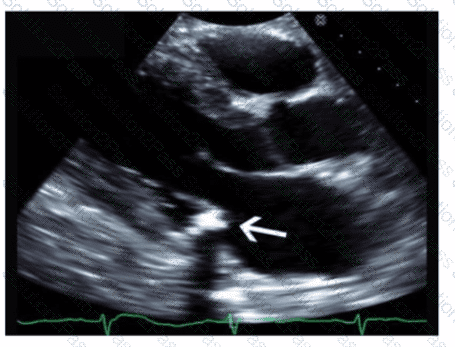

Which echogenic structure is indicated by the arrow on this image?